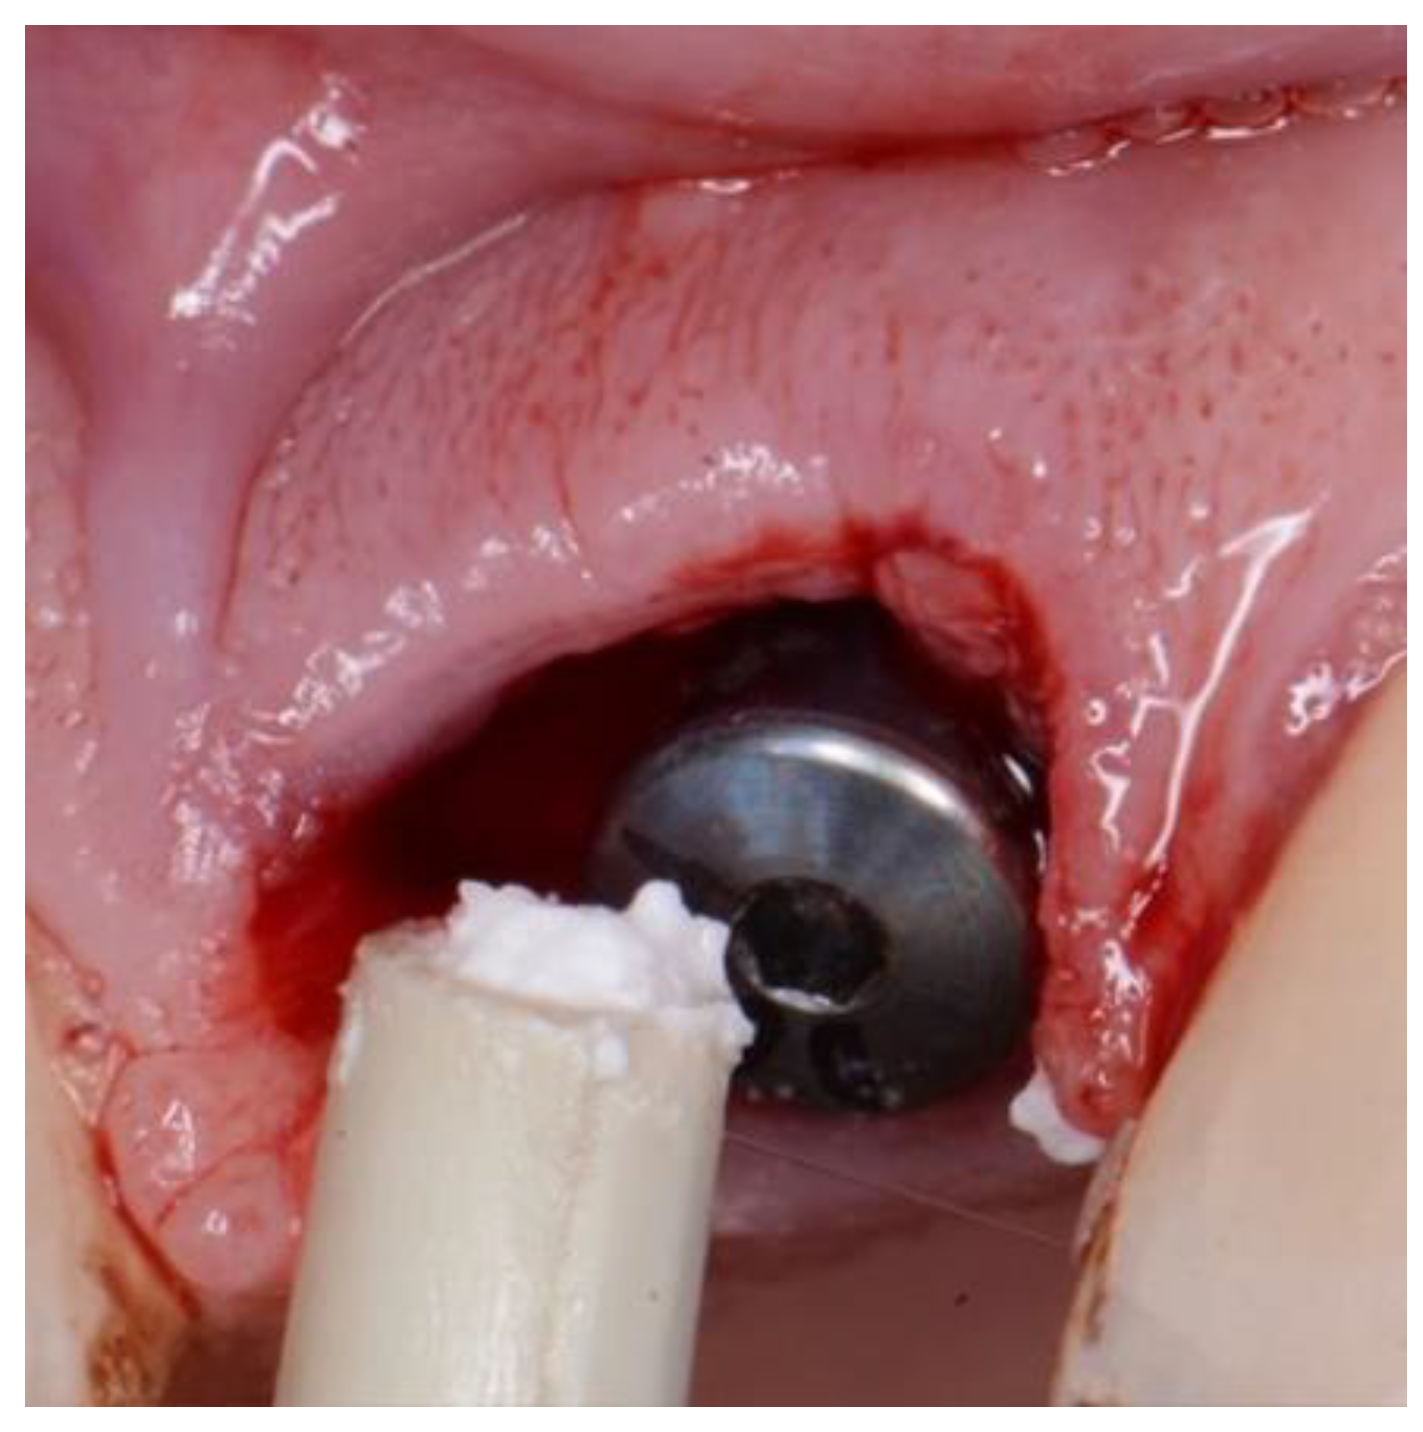

Figure 5. EthOss placement into circumferential jump gap.

Preprints 86078 g004

Figure 7. Showing set Ethoss in circumferential jump gap and Cervico Temp Crown.

Preprints 86078 g006

2.1. Clinical procedure

The surgical treatment protocol involved minimally traumatic tooth extraction. Residual socket debridement using both degranulation burs and sharp curettage. The osteotomy undersized by at least 0.5mm in circumference to allow placement of the novel body-shift implant of case-specific choice, 3.0 to 5.0mm from the labial free-gingival isthmus margin. A minimum immediate primary stability of 35ncm was required to facilitate immediate full contoured provisional restorations in non-occlusion [21]. The circumferential jumping gap was filled with the novel alloplastic bone augmentation material (EthOss. EthOss Regeneration Ltd, Silsden, UK). Screw- retained provisional restorations were fabricated from direct pick up of PEEK or Titanium temporary cylinders (Southern Implants PTY, SA) These were adjusted to non-occlusion in centric and excursions. The emergence profile of the provisional screw-retained restorations is not only important for particulate graft retention but also to adapt and preform the soft tissue. [22] Here the Cervico system (VP Innovato Holdings Ltd, Cyprus) was used by one study centre, whilst free-hand or in-house laboratory manufactured provisional shell crowns were used by the other centres. A concave subgingival emergence profile was obtained in all cases.